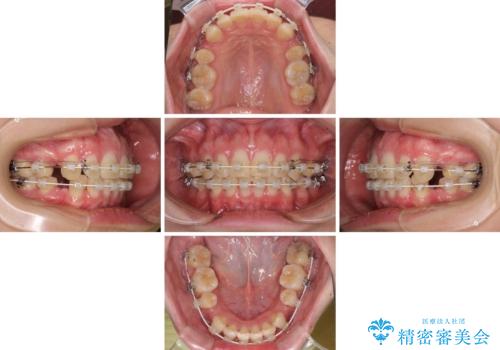

- 矯正装置

- 審美装置

左右ともに下顎に対して上顎歯列が前方位にある上顎前突であったので、上顎歯列全体を後方に移動させることで上下咬み合わせを改善し、その上で抜歯矯正により口元の突出感を改善させていきました。

口元を積極的に引っ込めるために、上下左右の小臼歯計4本を抜歯することとしました。

咬み合わせが深いため、咬み合わせの高さを向上させながら口元を下げることとしました。